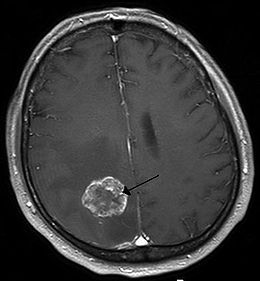

「多型性神經膠母細胞瘤」為最常見也是最惡性的膠質細胞瘤,台灣每年新增約200餘名病例,約占惡性腦瘤中4成比例,好發年齡為50至60餘歲。此種腦瘤具高度侵犯性,惡化極快且容易復發,患者平均存活率僅15個月,5年存活率亦低於10%。

現行治療方法多於手術部分切除後,針對殘留部分投藥進行化療及放射治療,但復發率仍接近100%。當前最有效的藥物Temozolomide僅能延長2.5個月的存活率,然所費不貲,單月療程就須花費20萬元。